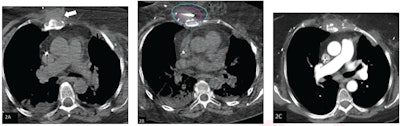

(A) Axial noncontrast CT chest image shows soft tissue mass in the anterior chest wall (arrow). The lesion was treated by percutaneous cryoablation. (B) Intraprocedural axial CT image obtained during cryoablation. The pink outline represents the target lesion and the blue outline represents ice ball. Based on review, the procedure was classified as achieving adequate ablation. (C) Axial contrast-enhanced CT chest image, obtained three months after ablation (patient’s first follow-up exam), shows involution of the target lesion without evidence of residue. Image courtesy of the ARRS.